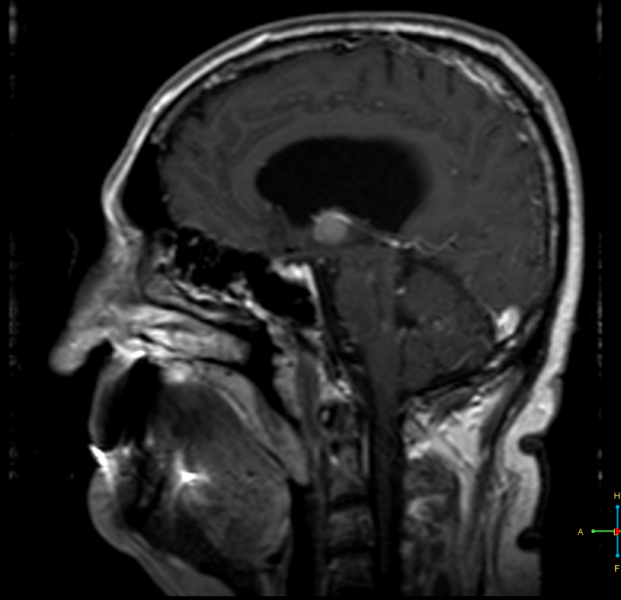

Ασθενής 63 ετών, προσέρχεται λόγω αναφερόμενων από το οικείο περιβάλλον διαταραχών βάδισης, πρόσφατης μνήμης και προσωπικότητας, συμτωματολογία αρχόμενη προ τριετίας.Υπεβλήθη σε μαγνητική τομογραφία εγκεφάλου η οποία ανέδειξε κυστική εξεργασία στο κατώτερο τμήμα της τρίτης κοιλίας (18x16x14mm), χαμηλού σήματος στις Τ2 ακολουθίες και υψηλού σήματος στις Τ1 (ως επί κολλοειδούς κύστης). Ο ασθενής αντιμετωπίστηκε αρχικά συντηρητικά, υπό παρακολούθηση με ετήσιο έλεγχο με μαγνητική τομογραφία. Από το περιβάλλον αναφέρεται προοδευτικά επιδείνούμενη συμτωματολογία κατά το τελευταίο εξάμηνο, για την οποία και αποφασίστηκε χειρουργική αντιμετώπιση.

Προεγχειρητικός απεικονιστικός έλεγχος